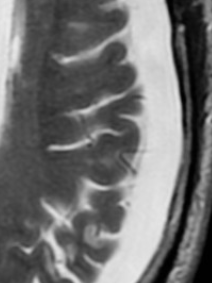

Aigu, Sub-aigu, Chronique

• Aigu = Hyperdense

• Subaigu = Isodense

• Chronique = Hypodense